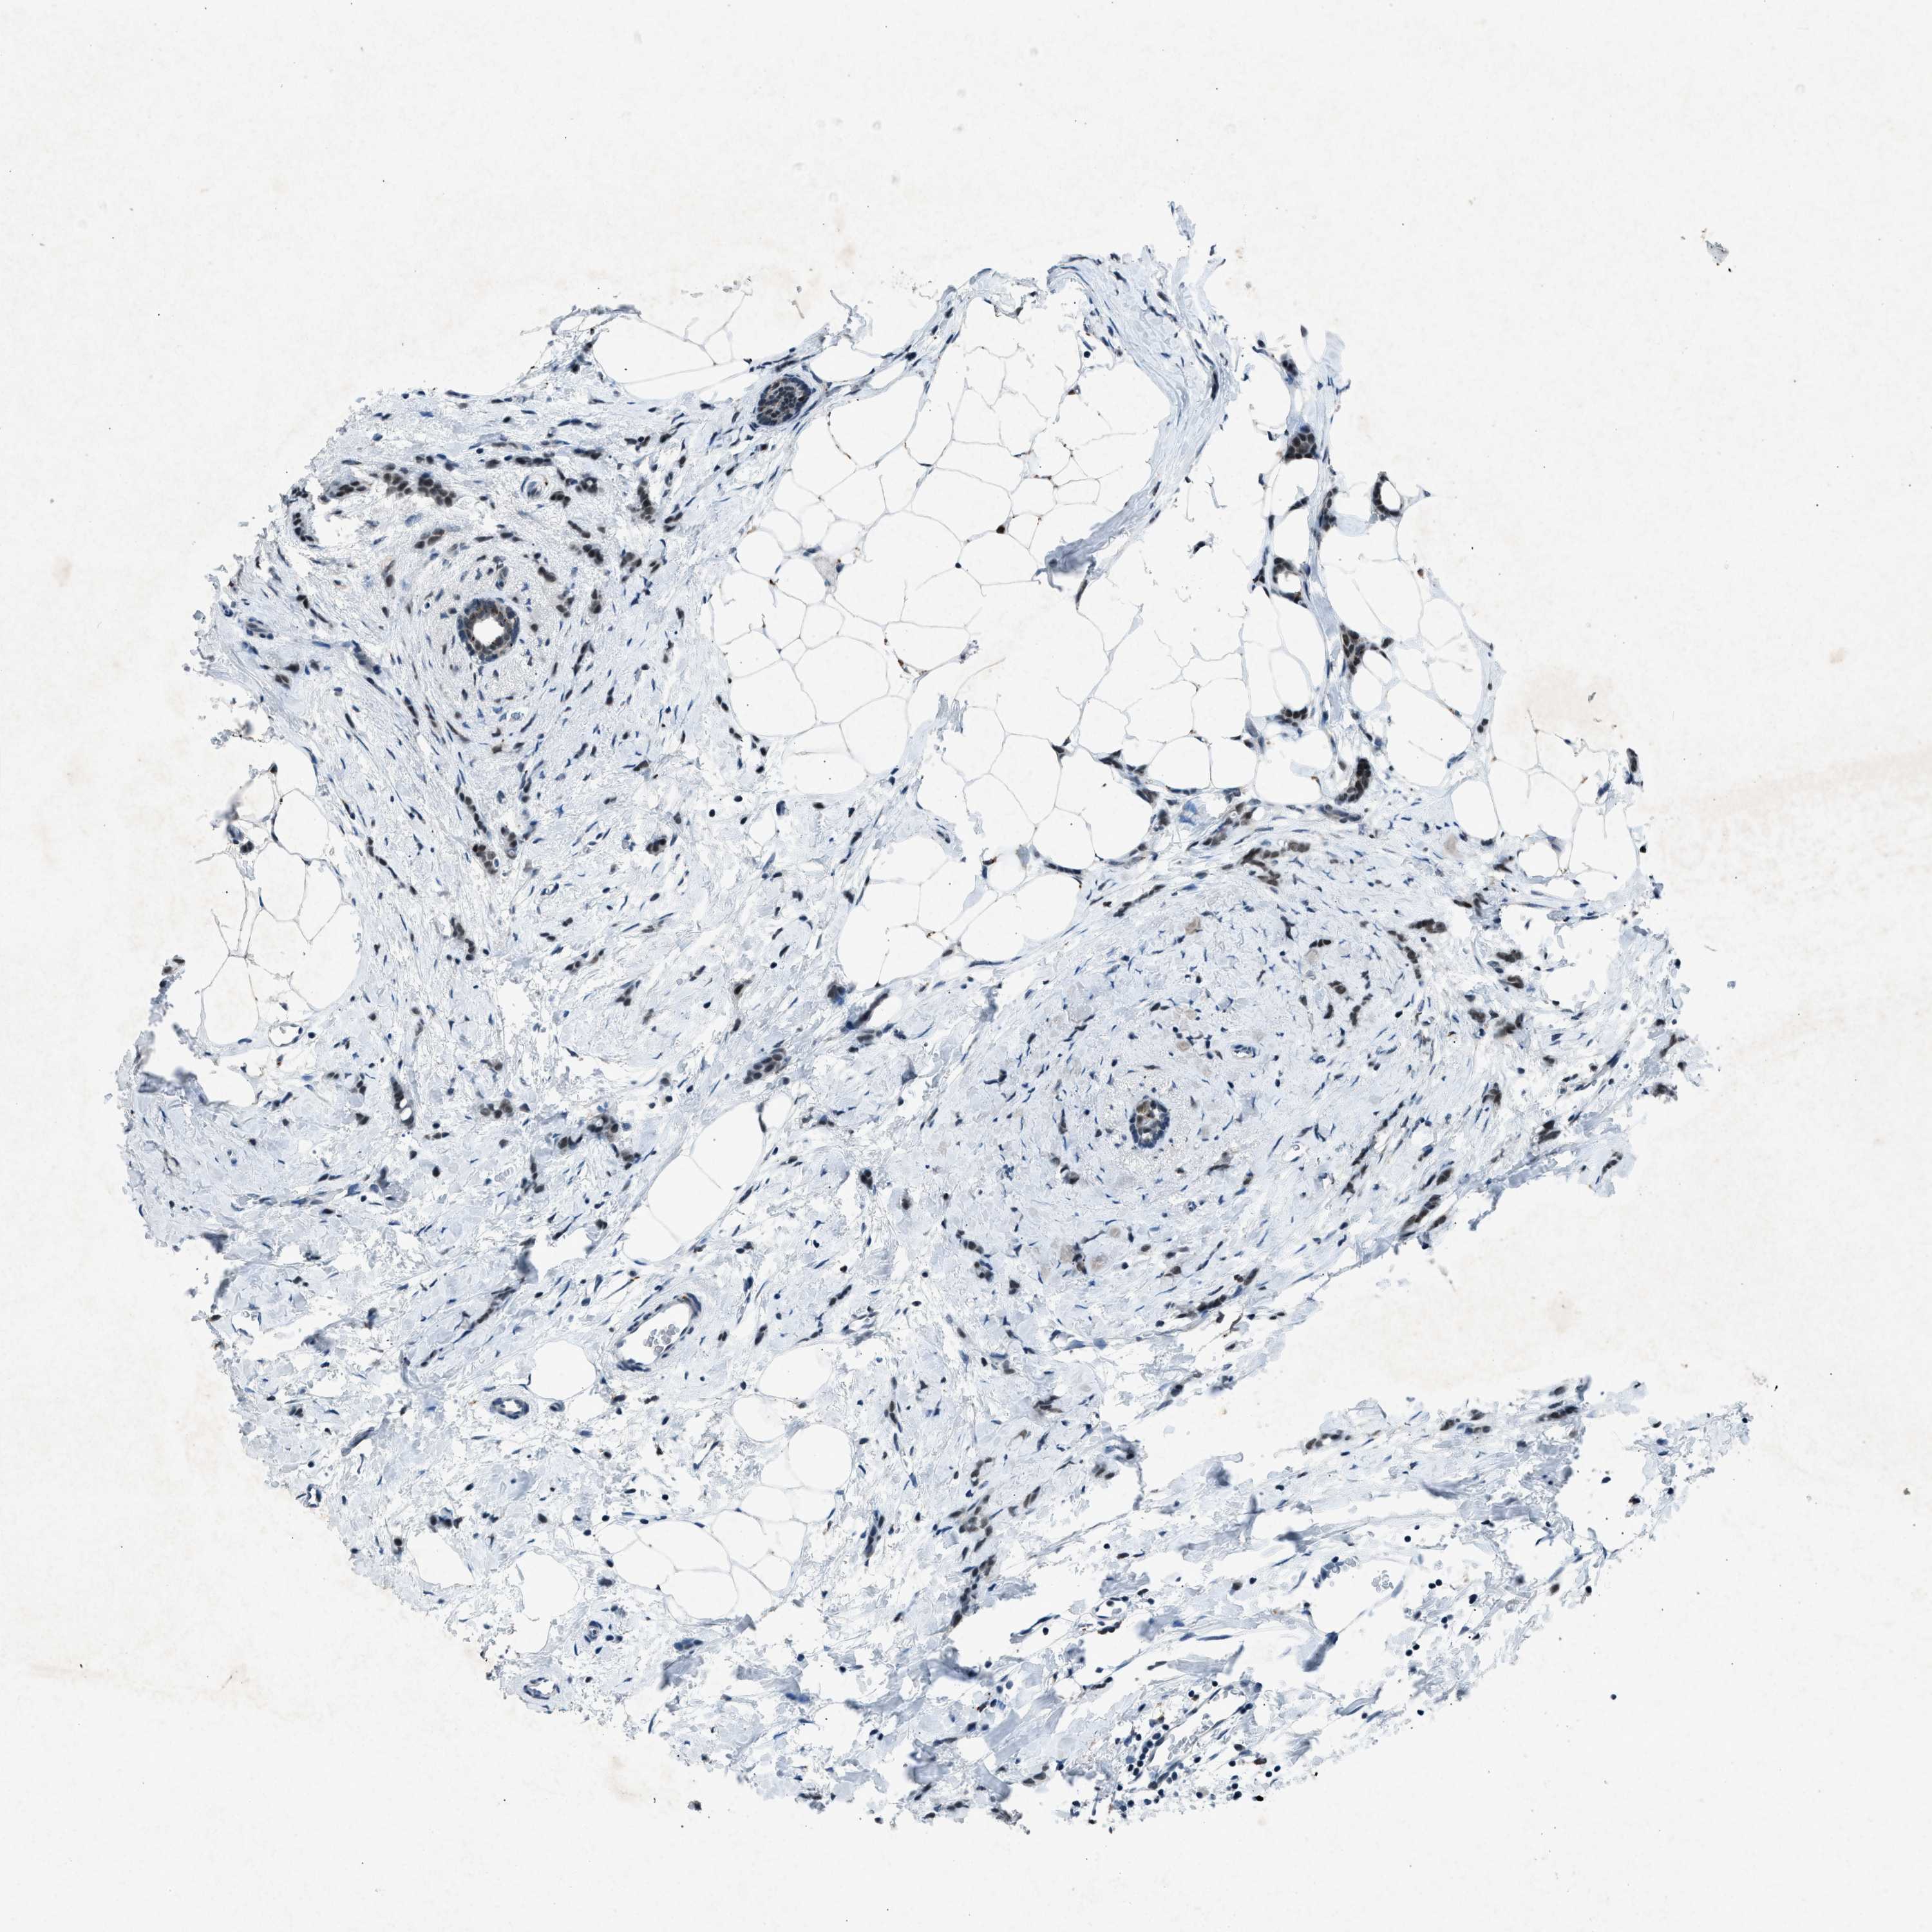

BRCA TCGA BRCA VALIDATION PROTEIN EXPRESSION